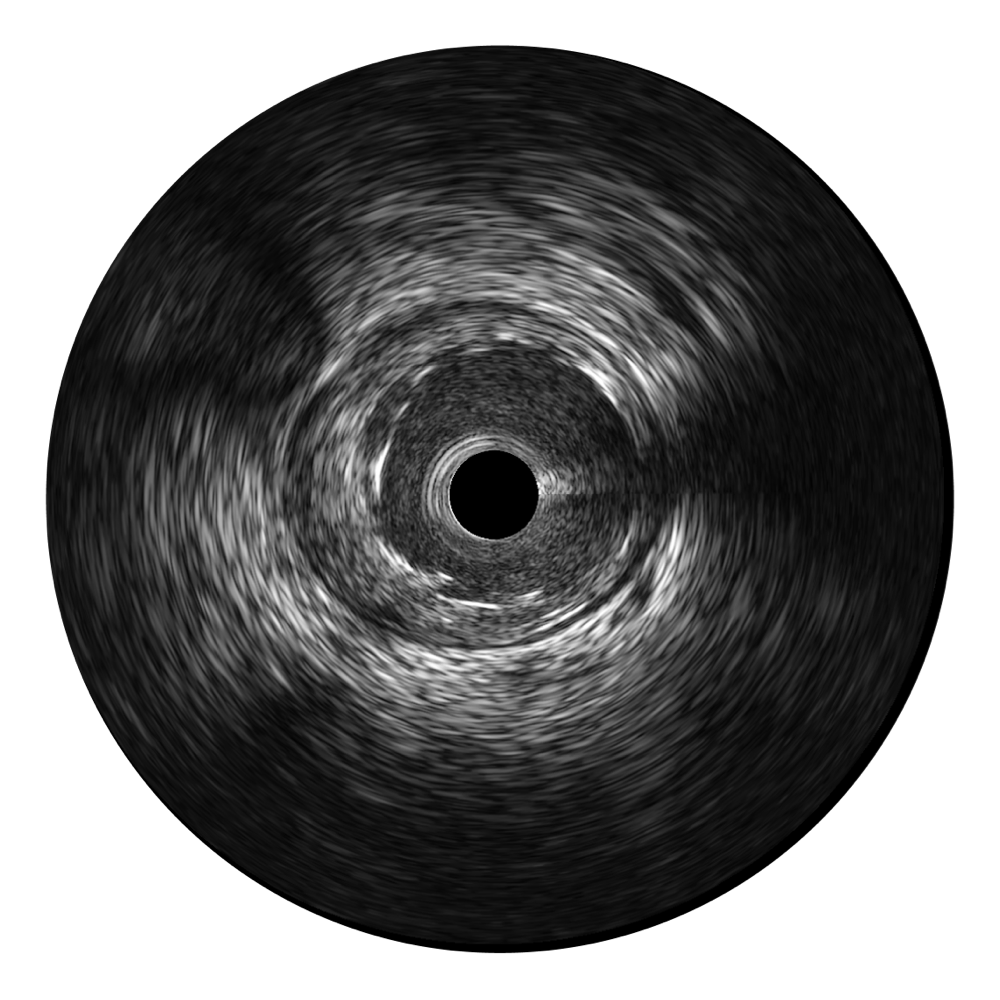

新葡的京集团8814检测站宽频IVUS图像

对比传统IVUS导管成像,新葡的京集团8814检测站宽频IVUS图像的近场支架梁显影更细腻,远场中膜外血管仍清晰可辨,兼顾远中近,兼顾分辨力与穿透深度